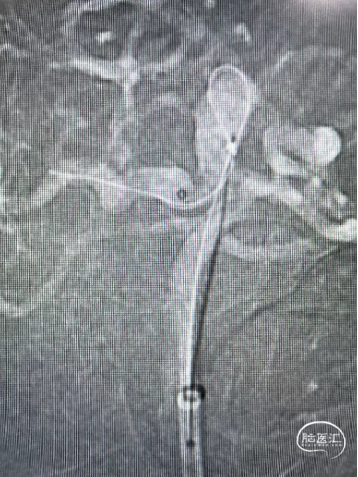

术中操作-预置支架导管+填圈:

预置支架导管

置入弹簧圈微导管

置入弹簧圈

填圈后通过微导管并释放支架

导丝通过&支架导管到位

释放支架:

支架到位

头端打开

中间打开

近端打开,后予以支架导管通过支架将其充分打开。

术后即刻复查:远端血管通畅、支架打开良好。

术后正位复查